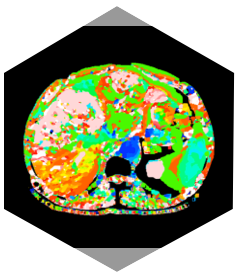

• „Regenbogen“-Algorithmus: Gemischtes Energiespektrum

» Röntgenspektrumdatenbank konfigurieren

» Datenkalibrierung konfigurieren

» Datenerfassungskorrektur